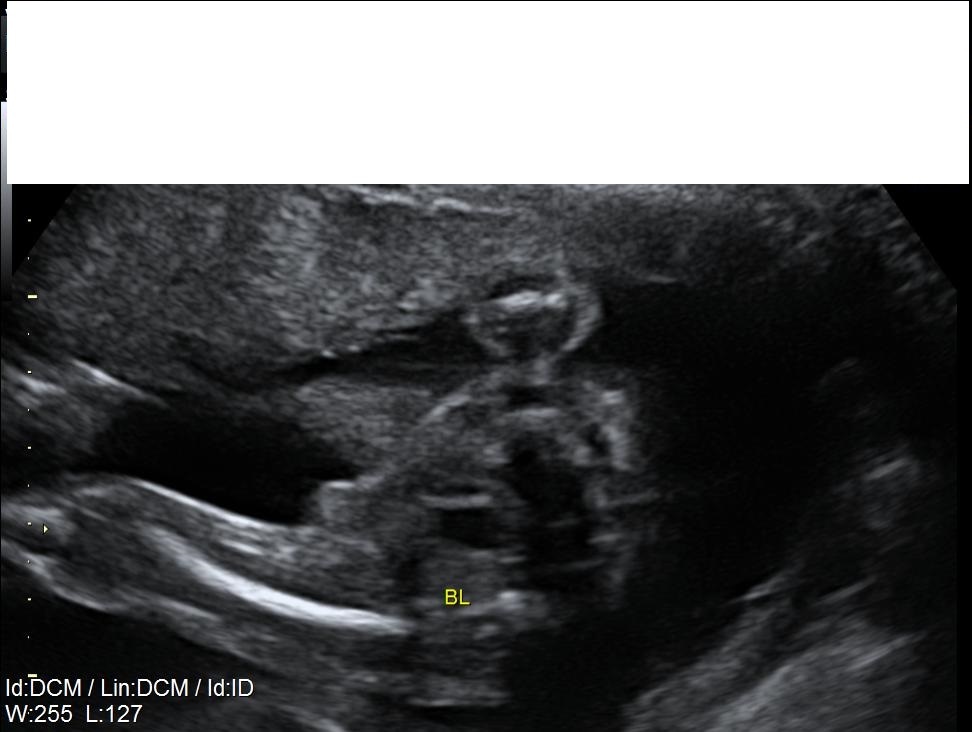

21 week 'bladder' shot..

It def looks like something is happening down there. I'd be inclined to say boy. But a top-shot isn't ideal for guessing. Still, I think a girly part would just look flat at this stage.

I guess i was just hopeful that it wasn't a proper shot from above as the bub refused to turn over during the whole scan apparently :)

Little wee Man!